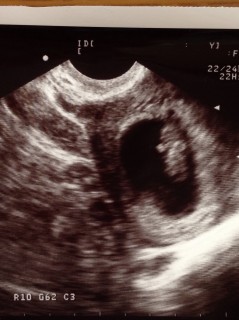

足がピクピクしていた! 初めて動いてるのを見ることができました♪ 大きさは23.0mmでした~!

手と足が生えて2頭身のまるで ドラえもん姿! うぅ~可愛すぎるぅ!!! 予定日確定★二週間後初健診★ 早く動いてるところ見たい!!! 悪阻ピーク気合で乗り切るぞぉ(T.T)